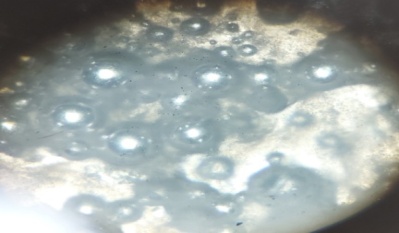

Fig. 5: Optical microscopic view

The microscopic view determines the particles are arranged in a cubic phase.

A light microscope (Edison Optics) is used to observe the cubosome gels at a magnification lens of 450X.

Fig. 9: Floating gel (Mag: 450X)